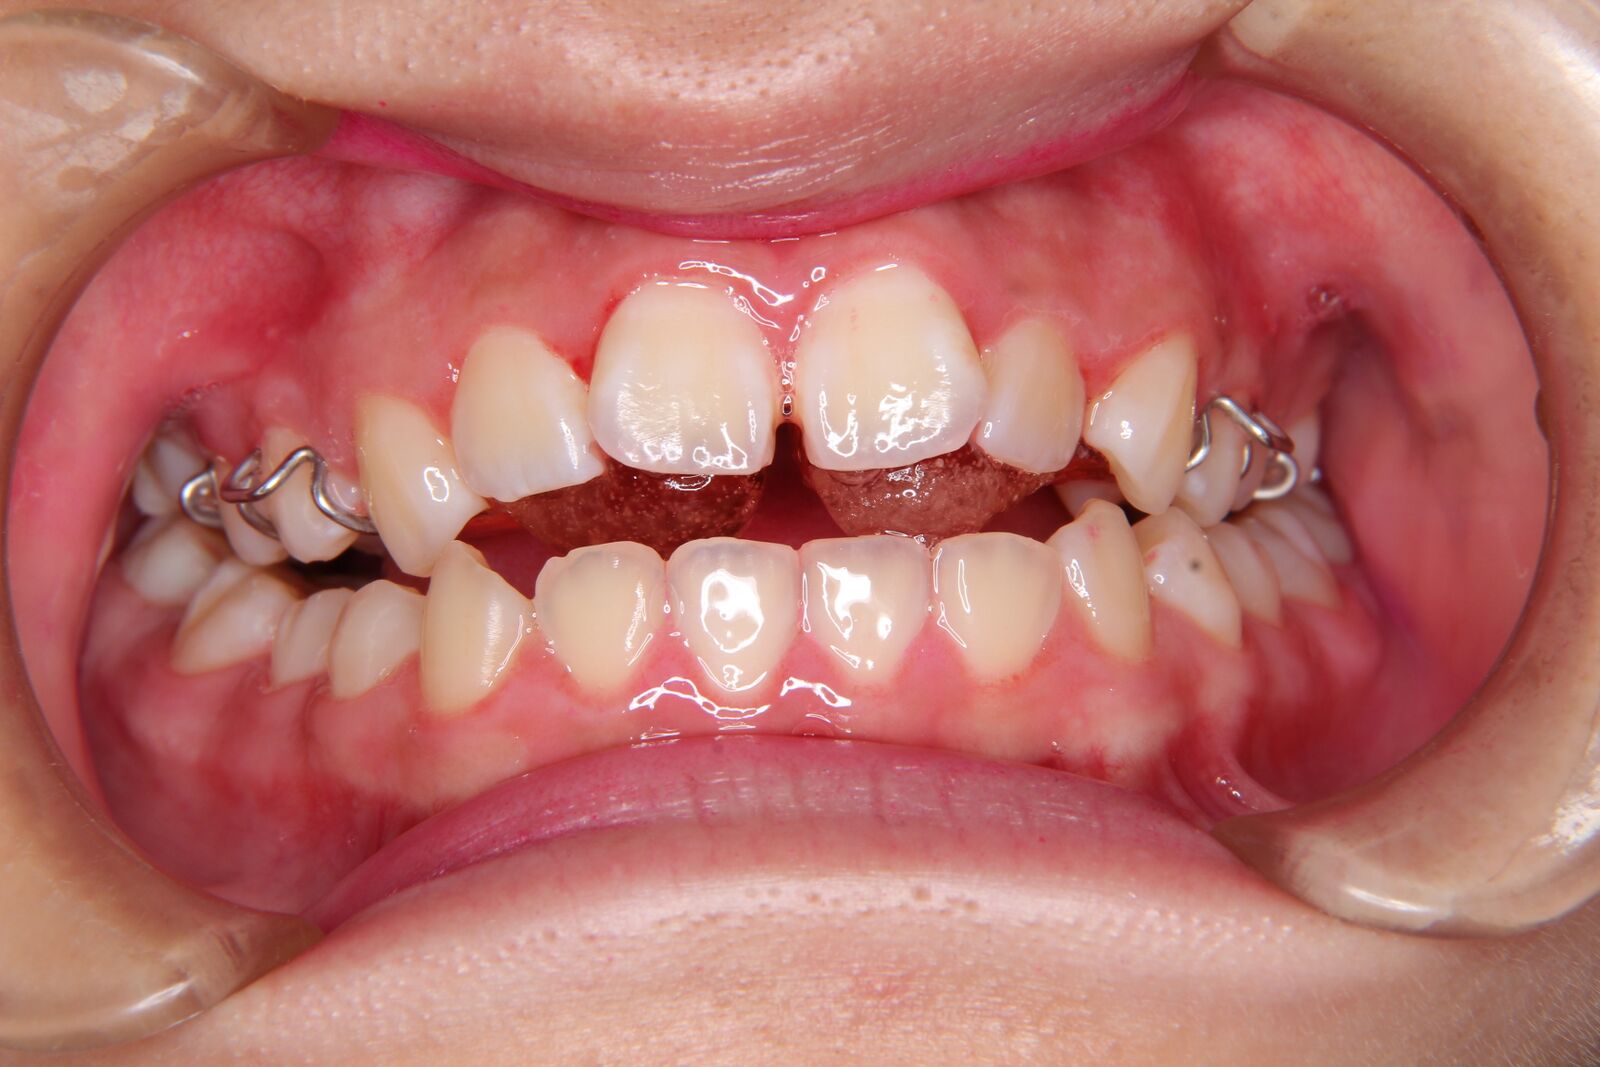

下顎の右側偏位のケースになります。

外科矯正による治療も検討しましたが、

・上顎歯列の拡大

・大臼歯部の干渉の改善による下顎位のコントロール

・左右の咬合高径の是正

により、外科なしで治療いたしました。